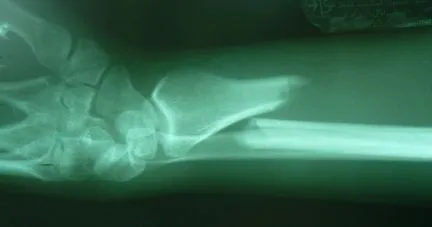

Back in Tampa, I ordered films of Alison's arm for presentation to her orthopedic surgeon.

Alignment is not perfect, but I was told that closed reductions involve a bit of luck, and no ground has been lost because healing does not commence for a few weeks. After a curbside conference, he indicated that the best plan for optimal alignment and minimal cast time would be a plate and screws, usually not palpable or visible from the outside after healing.

Dr. Gray used flouroscopy to confirm that the fracture margins were in perfect alignment, secured by three screws proximal and three screws distal to the fracture.

In fact, one view (below right) shows such tight apposition and such perfect alignment, that one cannot even see the fracture margins.

Dr. Gray checked all of her wrist bones (left), applied a new plaster splint and a new sling, and Alison's I.V. line was removed about 2.5 hours after it was inserted. What a great surgeon and professional team!